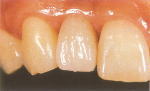

全ての歯を失った場合

普通の入れ歯はガタついたり、食べ物のかけらが入って痛かったり、かたい物も噛めなくて、大きく笑えないこともあります。

数本のインプラントを入れて、固定式の人工歯を入れることで入れ歯を入れることなく、天然歯のように自然に感じられます。